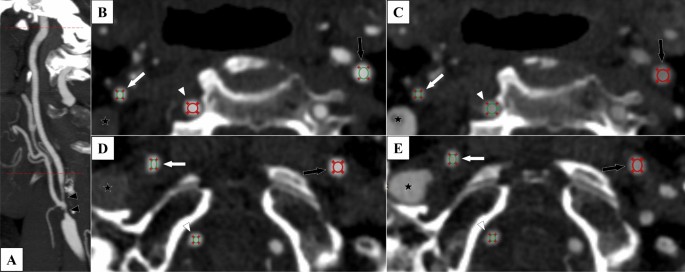

There were 12 measurement points for each case in a 3 × 2 × 2 × 2 approach: 3 arteries, 2 sides, 2 levels and 2 phases (Fig. 1). The three arteries were the two ICAs and the visibly largest of the two vertebral arteries. The two levels were: just beyond the stenosis (proximal) and immediately below the entry of the ICA into the skull base (distal). Hence, both proximal and distal level refers to the extracranial ICA beyond the stenosis. The two phases were considered as the arterial and venous phase. A circular region of interest (ROI) was placed and mean radiodensity within the ROI was assessed. The ROI was made as large as possible, but placed and sized so that the area within the ROI was homogenous in color, excluding the fuzzy edge on digital images around the artery lumen. Here, standard deviation (SD) of the Hounsfield units (HUI) within the ROI was measured for quality control, with high SD values signaling non-homogenous sample, prompting an adjusted ROI placement. All radiodensity measurements were done by KB, blinded to clinical information and the reference diagnosis. 18 randomly selected cases were also assessed by EJ to assess inter-rater reliability of radiodensity measurements (each with 12 measurement points, 216 assessments). EJ was also blinded to clinical information and reference diagnosis when performing these assessments.

The 12 measurement points in biphasic CTA exams. Case with right-sided near-occlusion without full collapse. 7 s between arterial and venous phase. ROIs placed to avoid the fuzzy edge around the artery. (A) Sagittal view with cervical levels (proximal and distal) marked with red dotted lines. Note that the proximal measurement still refers to the artery beyond (distal to) the stenosis (black arrowheads). (B) Arterial phase, proximal level. 488, 542 and 535 HU in right ICA (white arrow), left ICA (black arrow) and vertebral (white arrowhead). (C) Venous phase, proximal level. 351, 274 and 332 HU. Note the filling of the right jugular vein (black star with white rim). (D) Distal level, arterial phase. 486, 521 and 477 HU. Note the non-intuitive change in vertebral HU between proximal and distal phase that shifts the direction of v-correction from − 47 to + 9 HU whereas c-correction is more intuitive (− 54 and − 38 HU). (E) Distal level, venous phase. 379, 343 and 386 HU.